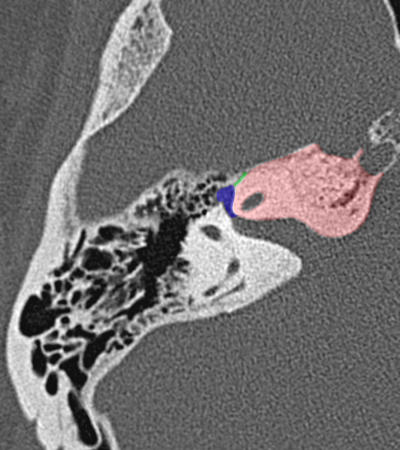

Radioanatomie du rocher sur coupes TDM

Différentes coupes de référence (A. Attyé 2013)

Coupe axiale passant par le canal semi-circulaire supérieur Coupe axiale passant par le canal semi-circulaire latéral Coupe axiale passant par le modiolus de la cochlée Coupe axiale passant par la fenêtre ronde Coupe axiale passant par le ganglion géniculé Coupe axiale passant par l'articulation incudo-malléaire Coupe axiale passant par la partie pétreuse de l'artère carotide interne Coupe axiale passant par le nerf tympanique

Coupe axiale passant par le foramen styloïde Coupe coronale passant par le muscle tenseur du tympan Coupe coronale passant par le recessus epitympanique Coupe sagittale passant par le segment mastoïdien du nerf facial coupe sagitalle oblique passant par le canal semi-circulaire supérieur (plan de Pöschl) Reconstruction axiale passant par le plan de l'étrier Coupe axiale passant par les apex pétreux